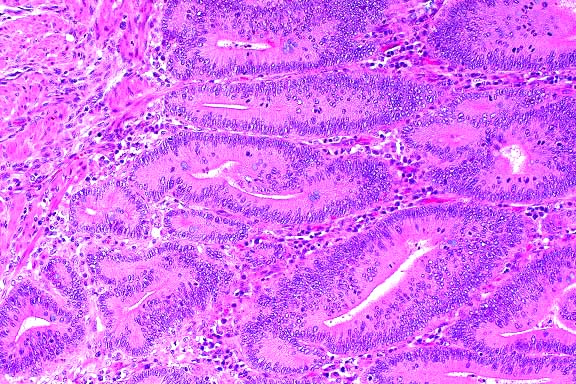

- On histopathologic examination, the ileal mucosa is diffusely

thickened by elongated, branching, hyperplastic crypts lined

by immature enterocytes. Warthin-Starry stained sections reveal

large numbers of small curved bacteria within the apical cytoplasm

of crypt and villar enterocytes. Sections of ileum sent for PCR

analysis using primers for porcine Lawsonia intracellularis were

positive.

- Case 22-2. Small intestine. Crypts are tortuous and

crypt epithelium is piled up and contains frequent mitotic figures.

Low numbers of macrophages and lymphocytes expand the lamina

propria.

- Conference Note: Proliferative enteritis or enteropathy

occurs in a number of animal species. Among domestic animals,

the disease is economically important in swine. In laboratory

animals, the condition is an important cause of enteritis in

hamsters. The etiology of the proliferative enteropathy in swine

remained unknown until recently when it was identified as Lawsonia

intracellularis. An organism nearly indistinguishable from L.

intracellularis has also been isolated from hamsters. Organisms

similar to L. intracellularis have been identified in lesions

of proliferative enteritis/colitis in rabbits, deer, ostriches,

horses, and ferrets; the organisms are closely related to L.

intracellularis.

- There is some variation among affected species in the location

of gross lesions. Lesions have been reported in the ileum of

horses, sheep, ostriches, guinea pigs, rabbits, hamsters, and

swine; in the stomach and ileum of dogs; in the cloaca of emus;

and in the colon of foxes, rats, and ferrets. Histologically,

the disease is characterized by crypt hyperplasia and numerous

small, curved, intracellular bacteria in the apical cytoplasm

of infected enterocytes, usually only visible with silver stains

(such as Steiner's or Warthin-Starry methods). Thus, despite

the variability in location of gross lesions, enterocyte proliferation

and intracellular organisms are the two common histologic features

of proliferative enteropathy in animals.